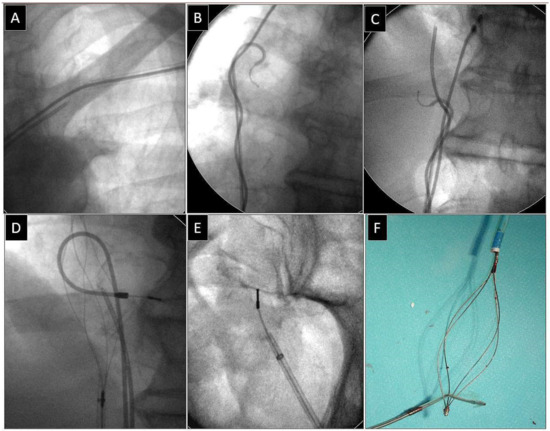

2.2.5. Extraction of Leads with Their Proximal Ends Migrated into the Cardiovascular System